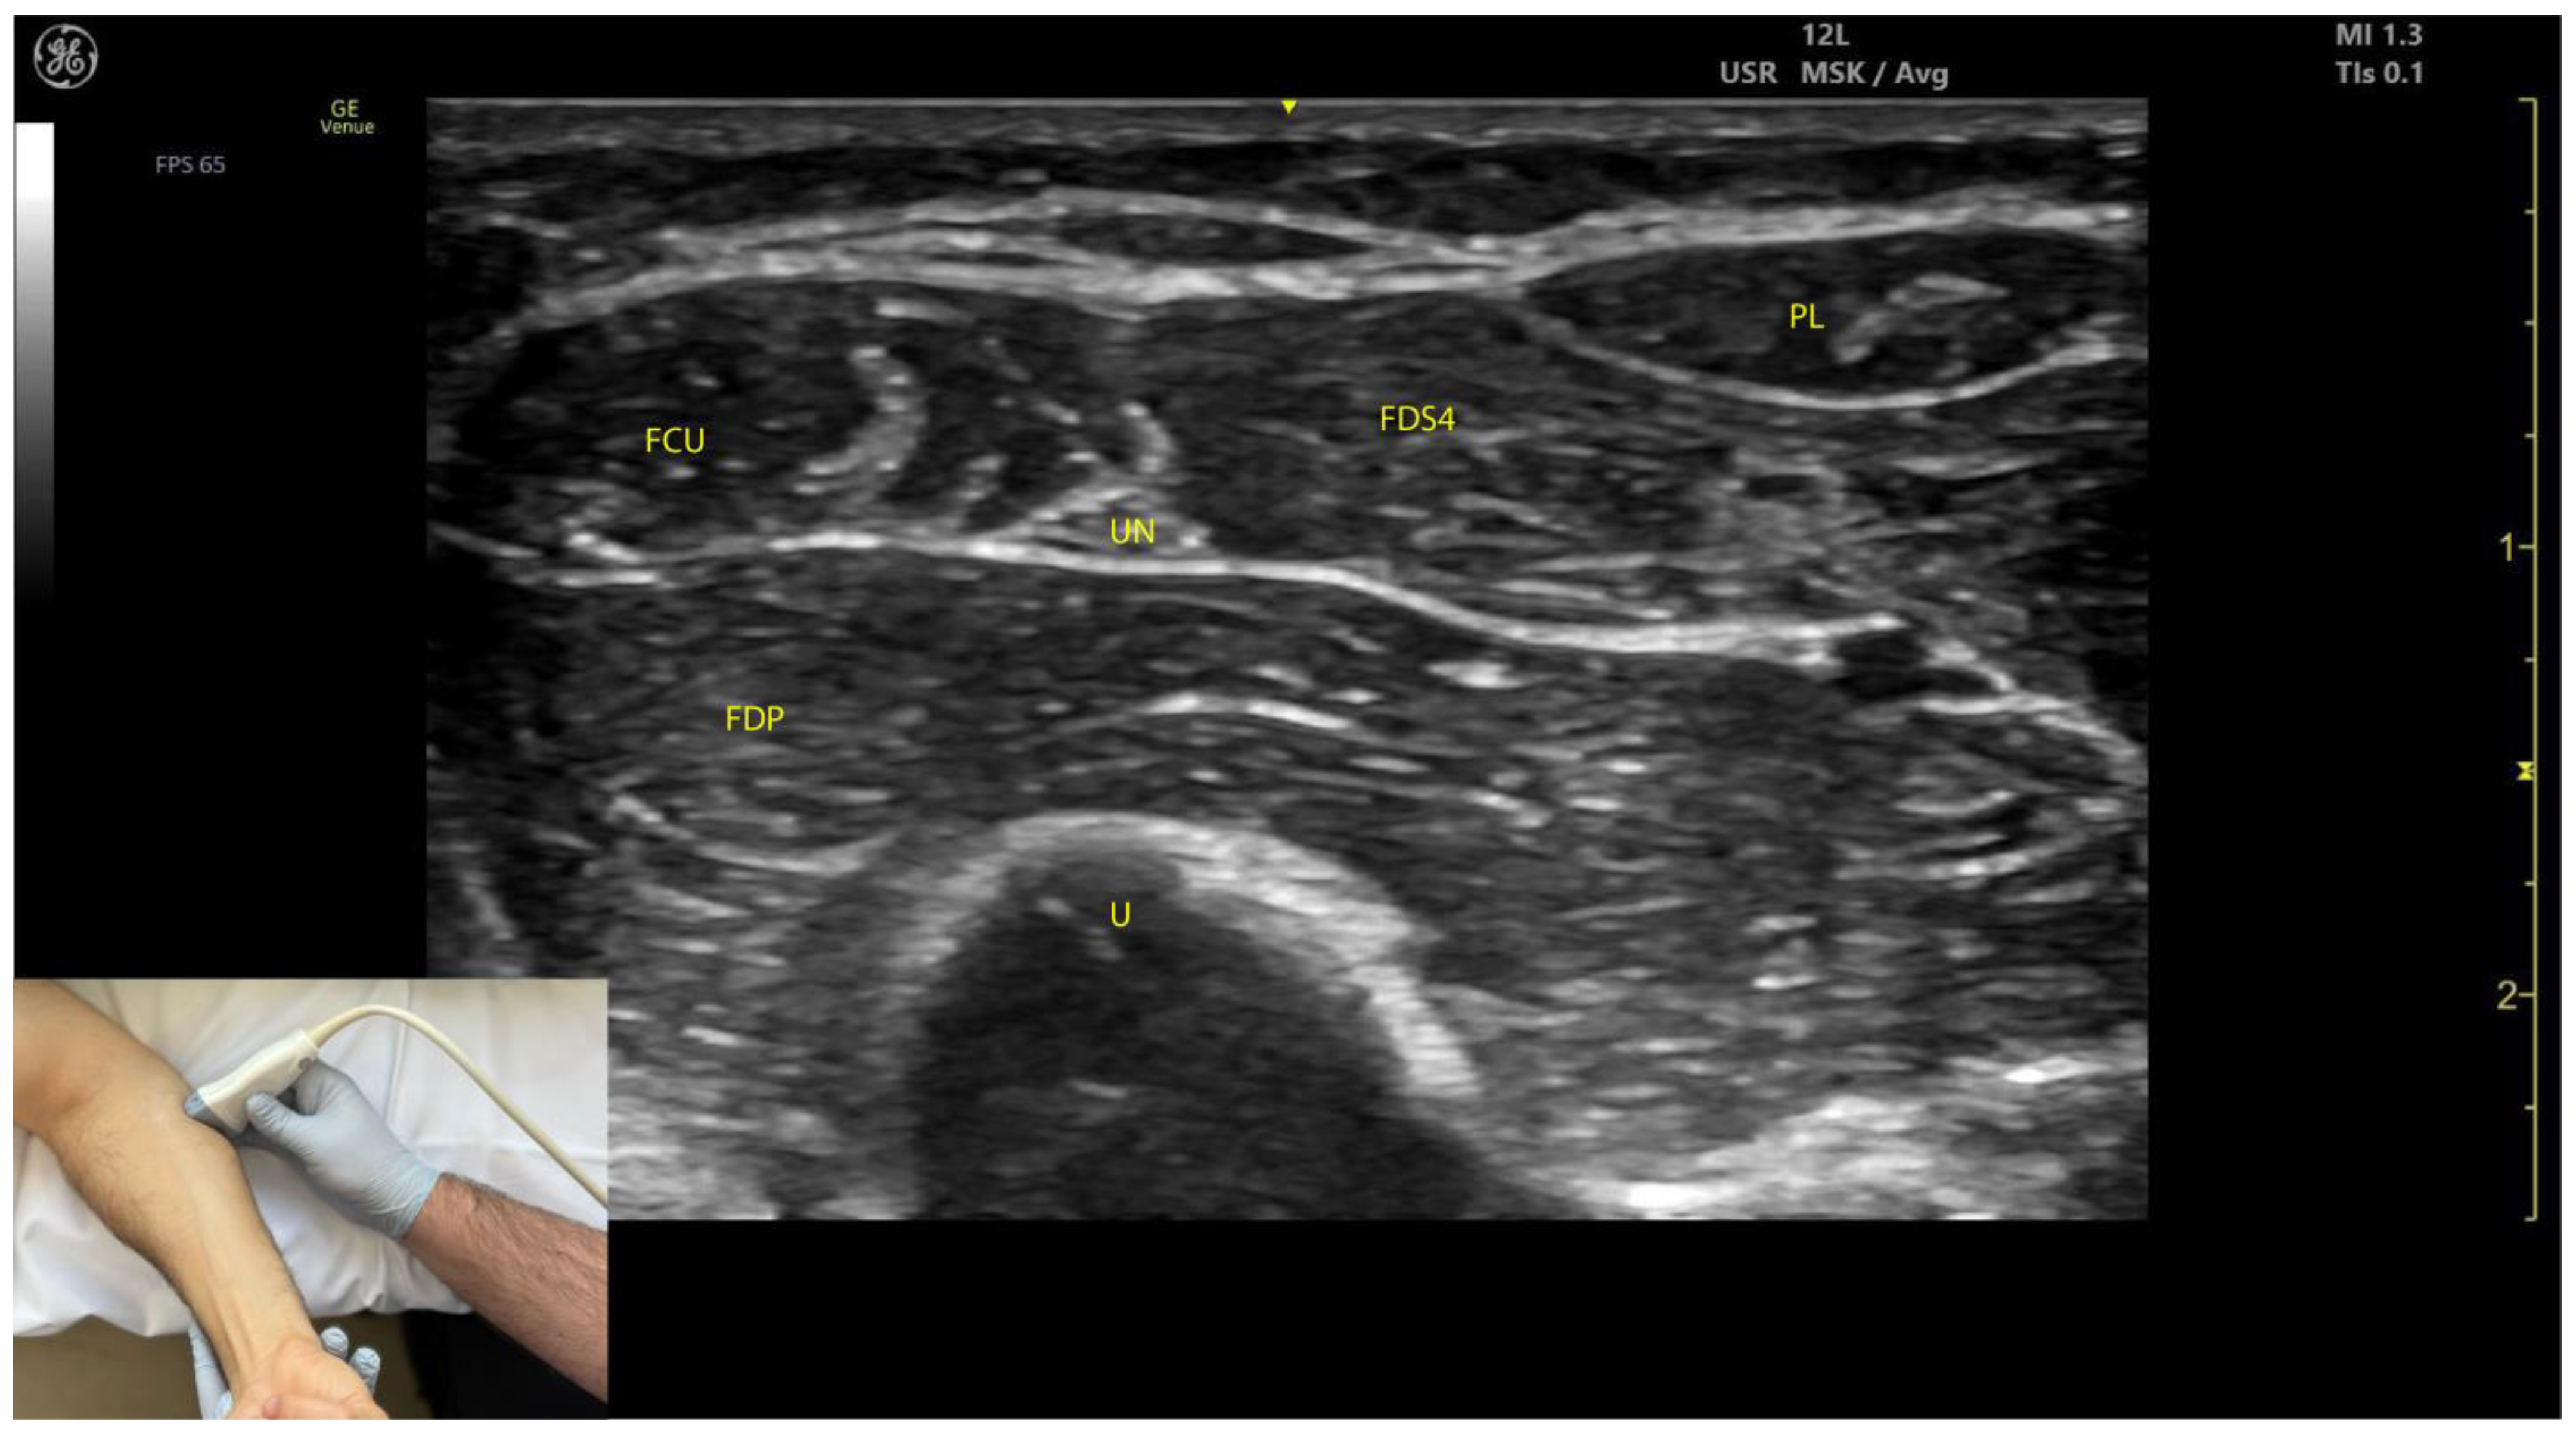

2.3.3. Key Ultrasound Landmarks (Figure 3)

- Muscle position: The FCU is the most medial muscle mass in the flexor compartment of the wrist, located on the volar aspect of the forearm [24].

- Internal fascia: The intramuscular fascia, often referred to as “cloud fascia” due to its cloud-like appearance, separates the humeral and ulnar heads of the FCU. This fascia can be visualized from the muscle’s origin at the medial epicondyle, extending distally until the FCU transitions into its tendon [23].

- Ulnar nerve (Video S2): The ulnar nerve is located deep to the FCU approximately 2–3 cm distal to the elbow crease. When scanning cranially toward the medial epicondyle, the ulnar nerve can be seen passing between the humeral and ulnar heads of the FCU as it enters the volar compartment of the forearm [25,26]. Scanning distally reveals a gradual decrease in FCU muscle size and an increase in FDP muscle size. At the mid-forearm level, the ulnar nerve joins the ulnar artery, and both structures descend together into the distal forearm toward Guyon’s canal [26].

- External fascia: The external fascia distinctly demarcates the FCU from adjacent muscle masses, facilitating precise BoNT-A injection.

- Dynamic evaluation: Contraction of the FCU is observed during wrist flexion and adduction maneuvers.

2.3.4. Clinical Implications and Injection Strategy

- Electromyographic studies indicate that the region with the highest concentration of motor plates in the FCU is located approximately 32% along the line connecting the most prominent point of the medial epicondyle to the pisiform bone, corresponding to about one-third of the muscle’s length [22].

- In our clinical practice, ultrasound is used to precisely target the motor point by identifying the point of maximum muscle thickness. The transducer is positioned transversely on the volar aspect of the forearm, approximately 4 cm distal to the elbow crease in the ulnar portion, ensuring accurate and effective delivery of BoNT-A.